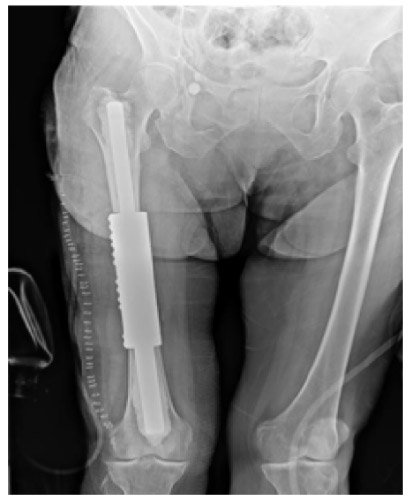

Post-surgery: The X-ray shows an intercalary cemented tumor prosthesis.